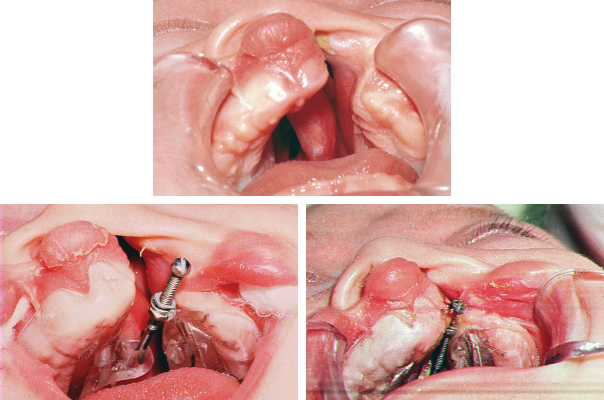

63 ○ Presurgical infant orthopedics (PSIO) is performed in an attempt to improve the lip and palate repair by realigning the displaced maxillary bony segments found in clefts. ○ Passive appliances are acrylic plates that are adjusted frequently to apply a combination of pressure on one side and relief on the other that directs the bony growth of the maxillary segments into alignment. ○ Active appliances are fixed to the bony segments with pins or screws, and the segments are aligned with jackscrews and elastic bands. ○ The addition of nasal extensions by Grayson and his colleagues led to the development of nasoalveolar molding. ○ PSIO has generally been shown to be effective in improving the alignment of the maxillary segments before lip and palate surgery. ○ Whether PSIO improves long-term outcomes of nasolabial appearance, dental alignment, and palatal function when compared with patients who do not have PSIO is a subject of considerable disagreement. C. Kerr McNeil1–3 first described presurgical infant orthopedics (PSIO) in cleft care in 1950 when he introduced the concept of using orthodontic appliances to realign the maxillary segments in infants with clefts of the lip and palate. He proposed that repositioning the maxillary segments would facilitate the surgical repair of the lip and palate and improve symmetry of the maxilla, lip, and nose. The practice of PSIO was founded in the belief that repositioning the palatal segments and dental arches will facilitate the surgical repair of the lip and palate, ease alveolar bone grafting, and simplify orthodontic treatment. Proponents felt that repositioning the premaxilla and lateral palatal shelves would prevent the maxillary retrusion commonly seen in patients with clefts. They also hypothesized that the improved maxillary alignment would also allow concurrent symmetric growth of the mandible that, in turn, would allow for a more stable correction of the dental malocclusion.4 Bilateral clefts appeared to be particularly suited to the technique. Appliances were used to reposition the premaxilla posteriorly after expanding the lateral segments, thereby facilitating the lip repair.5,6 Although the theoretical advantages of PSIO allowed the technique to gain popularity, it wasn’t until its use in conjunction with primary alveolar bone grafting that it became widely practiced.7 Despite early reports of impaired maxillary growth with primary alveolar grafting, reports of favorable outcomes existed as well.5,6,8–10 Burston,5,6 an orthodontist from England and strong proponent of early bone grafting in combination with PSIO, stated that the main objective of PSIO with primary bone grafting was to prevent palatal collapse, to maintain normal alveolar alignment, and to promote eruption of deciduous teeth with appropriate dental relationships. He also claimed these patients had improved respiration, feeding, speech, and middle-ear function, although these claims were certainly not grounded in sufficient evidence. Before the advent of PSIO, some surgeons attempted to align the facial skeleton by performing premaxillectomies, either in infancy or in later childhood. These procedures resulted in severe underdevelopment of the midface, collapse of the maxilla, failure of growth of the prolabium, and loss of support for the upper lip.11 Fortunately, this procedure has been abandoned. Many terms have been applied to techniques of presurgical maxilloalveolar molding, soft tissue manipulation, or a combination of the two. Common terms include presurgical infant orthopedics, neonatal maxillary orthopedics, and nasoalveolar molding. The design and application of these appliances have varied considerably. Notable contributions to the field have been made by Hotz,8 Latham,12 Rosenstein,13 and Grayson et al.14 Appliances can be divided into two broad categories: passive and active. Passive appliances use acrylic plates that are constructed in a manner that applies pressure to the palatal segments in the direction of the desired movement and relief on the opposite side to accommodate the moving palatal shelf. The acrylic plates require frequent adjustments by the dentist or orthodontist to continue directing palatal growth. New appliances are made as needed to accommodate the growing maxilla (Figs. 63-1 and 63-2). Fig. 63-1 A, Passive acrylic appliance. B, Appliance in place. Fig. 63-2 A, Passive appliance built on a plaster model. B, Passive appliance with extensions attached to headband. Grayson et al14 added nasal extensions to the appliance to reshape the nostrils. Presurgical nasoalveolar molding (NAM), discussed in more detail in Chapter 64, addresses the soft-tissue derangements of the lip, palate, and nose. The technique not only aligns the maxillary segments but also takes advantage of the principles of tissue expansion and the malleability of the infant nasal cartilages to reshape and align the soft tissues. Columellar length and shape is improved, especially in bilateral clefts, and lip repair is thereby made simpler. Despite the obvious advantages, the cost-effectiveness and long-term efficacy of the technique are questionable. Active appliances, popularized by Latham, are fixed intraorally with screws, elastic chains, or plates used to apply direct traction forces to align the palatal segments (Figs. 63-3 and 63-4). Fig. 63-4 An active pin–retained device with a jackscrew used to approximate the maxillary segments. Controversy surrounds the use of PSIO as much now as it did in the 1960s, at which time Pruzansky criticized the widespread acceptance of PSIO, citing that many of its proponents relied not on evidence but on anecdotal reports and uncontrolled studies. In his paper “Presurgical Orthopedics and Bone Grafting for Infants With Cleft Lip and Palate: A Dissent,”15 Pruzansky pointed out that without well-designed, controlled studies, claims that the technique facilitated lip and palate repair and improved feeding, speech, and psychological outcomes could not be substantiated. He also drew attention to the fact that proponents of the McNeil method had limited evidence to support the dominance of the nasal septum as a growth force and had failed to consider the effect that repositioning the orbicularis muscle exerts on the dynamic palatal segments. Perhaps what was most important, he contested the notion that collapse of the maxillary arch is an undesirable side effect of primary cheiloplasty. He felt that preventing medialization of the palatal shelves with interposition of a palatal splint would be detrimental to reestablishing velopharyngeal competence. Anatomic studies have demonstrated that the nasopharynx of the cleft side is wider than that of the noncleft side.16 After lip repair, medial movement of the maxillary arch narrows the cleft side nasopharynx to a more normal dimension, an effect considered desirable. More recently, Winters and Hurwitz17 concluded that the objective evidence in support of PSIO is lacking. To consider the advantages and disadvantages of PSIO, understanding the changes that occur after the lip and palate are repaired without the use of PSIO is necessary. Mazaheri and colleagues18–21 of the Lancaster Cleft Palate Clinic demonstrated the effect that primary lip closure exerts on the palate in a longitudinal analysis of patients with unilateral cleft lip and palate: • The palatal cleft narrows as the palatal segments are repositioned. • Downward growth and change in angulation of the palatal segments accounted for by the inherent medial growth of the palatal shelves occurs. • The greater and lesser palatal segments continue to undergo favorable change and repositioning with eruption of the deciduous dentition.

ACTIVE APPLIANCES